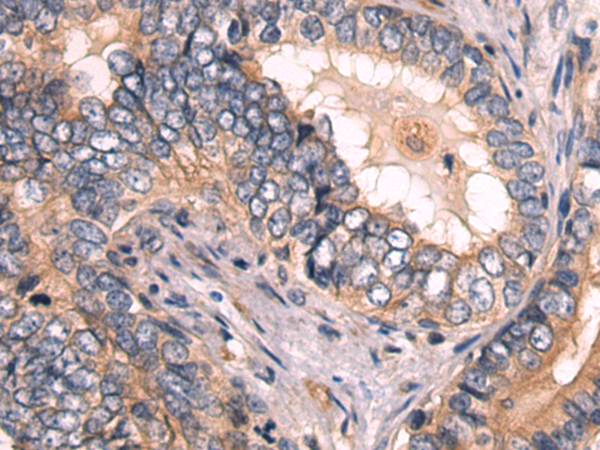

分类: 科研抗体货号: P09403别名: DVC1; PRO4323; spartan; C1orf124应用: IHC反应种属: Human, Mouse, Rat